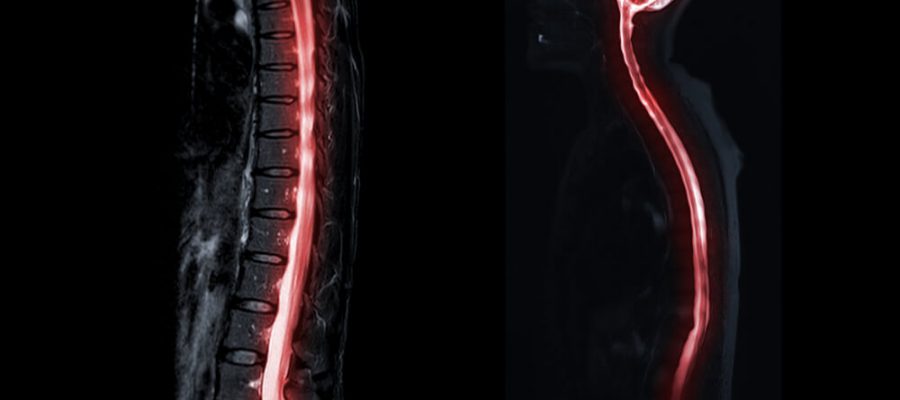

Genel olarak bu emar türü spinal vertebra adı verilen bölgelere yapılır. Bu bölgelerde bulunan hastalıkların teşhisinde kullanılır. Genel olarak emar çekimi yapılmadan önce kişilerin belirli hazırlık yapması gerekir. Kişilerde boyun fıtığı bulunup bulunmaması genel olarak bu işlem sonucunda ortaya çıkar.

Galenlab laboratuvar da bu işlem için gelen hastalardan sırt üstü yatması istenir. Genel olarak kişilerin hastalık bulunan bölgelerinden kesitler alınır. Daha sonra bu emar sonucunda hastalığın ne olduğu belirlenir. Bu işlem genel olarak oldukça önemli bir yere sahiptir.

Kişinin sırt üzeri yatması sonucunda bu emar türü ile boyun bölgesinden aşağıya doğru gözükür. Bu uygulamada herhangi bir radyasyon bulunmaz. Bu nedenle bu emar işleminin herhangi bir zararı bulunmaz. Bu nedenle kişilere tüm spinal mr çekimi oldukça önemli bir yere sahiptir.

Genel olarak bel fıtığı çeken insanlara emar çekimi yapılır. Bu emar çekimi sonrasında kişinin belinde bulunan fıtık meydana çıkar. Genel olarak doktorlar hastaların belirtileri üzerine emar çekimini uygun bulurlar. Aynı zamanda kişilerin omuriliğinde bulunan hastalıklar da emar sonucunda ortaya çıkar.